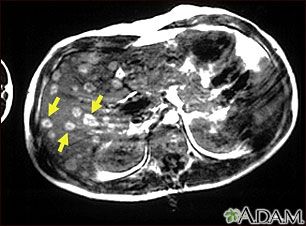

Once melanoma has been diagnosed, CT scans or other types of x-rays may be done to see if the cancer has spread.